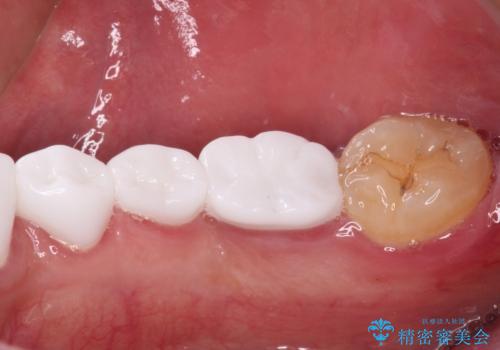

本来、あまりにも不自然な歯となるため、フルジルコニアクラウンを前歯に使用することは、咬合力が強すぎる場合を除き、ほとんどありません。

それでも、色調、形態ともに不自然なくらい真っ白な歯をご希望でしたので、患者様には大変満足していただきました。